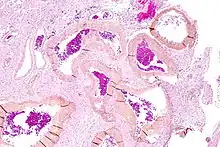

| Micrograph of an arteriovenous malformation in the brain. HPS stain. | |